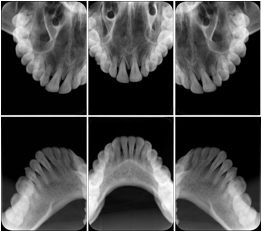

1. A patient in rural Canada visits a general ophthalmologist and is found to have diabetic macular edema. The general ophthalmologist would like to discuss the case with a retina specialist before performing laser surgery. A fluorescein angiogram is done with multiple retinal images taken in a timed series after an intravenous injection. The images along with a Structured Display are shared via a Health Information Exchange with a retina specialist in Calgary, who opens them using his Ophthalmology EMR software and consults via phone with the general ophthalmologist. Both physicians view the images in the same layout so the retina specialist can provide accurate guidance for treating the patient.

2. A patient in rural Iowa visits his primary care physician for management of diabetes. Three non-mydriatic (patient's eyes are not dilated) photographs are taken of the back of each eye, and forwarded electronically along with a Structured Display to an ophthalmologist in Iowa City. The ophthalmologist reads the photos in an agreed upon layout so there is no mistake about what portion of which eye is being viewed. The ophthalmologist is able to tell the primary care physician that his patient does not need to come to Iowa City for face to face ophthalmologic care, but that there is a particular view of the left eye that should be photographed again in 6 months.

Ophthalmic Retinal Study Structured Display

Figure OO-3. Ophthalmic Retinal Study Structured Display

3. A patient in rural Minnesota experiences sudden vision loss and goes to a general ophthalmologist, who acquires OCT images and forwards them electronically along with a Structured Display to a retina specialist six travel hours away. The retina specialist is able to view the images in the standard layout that he is comfortable with, and to confirm that the patient has a choroidal neovascular membrane. He determines that is would be worthwhile for the patient to travel for treatment.

OCT Retinal Study with Cross Section and Navigation Structured Display

Figure OO-4. OCT Retinal Study with Cross Section and Navigation Structured Display